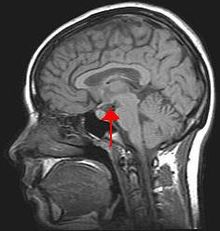

Der Hypothalamus (griech. ὑπό hypo „unter“ und θάλαμος thalamós „Zimmer, Kammer“) ist ein Abschnitt des Zwischenhirns (Diencephalon) im Bereich der Sehnervenkreuzung (Chiasma opticum). Medial wird der Hypothalamus vom dritten Ventrikel, kranial vom Thalamus begrenzt. Das Infundibulum, der sogenannte Hypophysenstiel, verbindet den Hypothalamus mit der Hypophyse, deren Hinterlappen noch als Teil des Hypothalamus bezeichnet wird. Der Hypothalamus bildet Effektorhormone, Releasing- und Inhibiting-Hormone, verschiedene Neuropeptide und Dopamin. Er steuert damit die vegetativen Funktionen des Körpers.